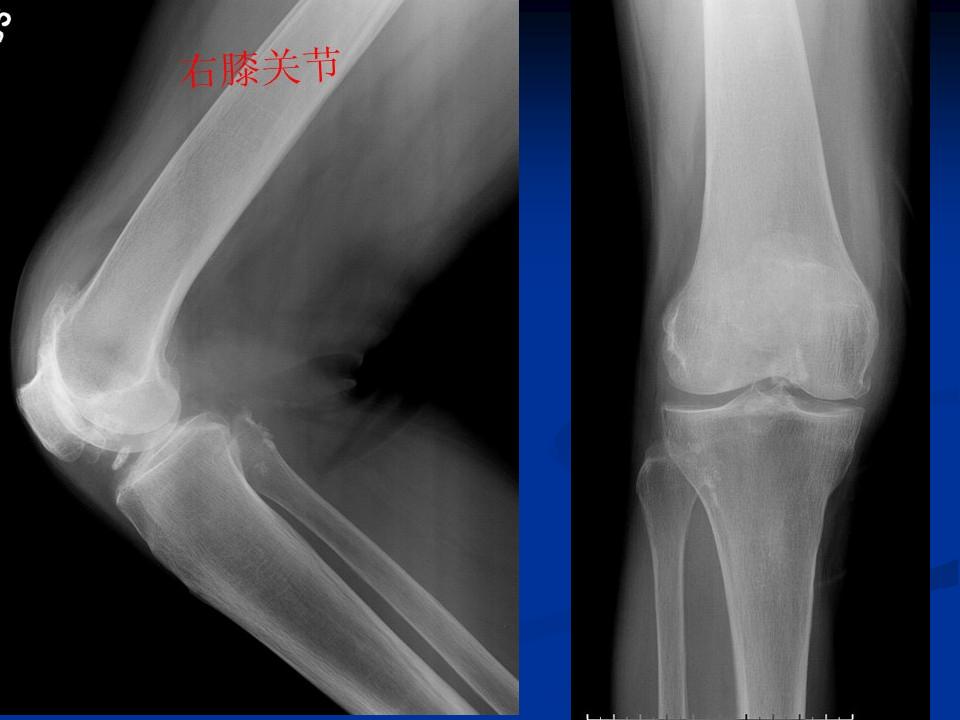

影像学检查 X线 四个方向X线影像 l 早期可无改变 l关节间隙变窄、不均匀、消失(成人<3mm; 老年人<2mm)。 l骨赘形成 l关节内游离体、骨质疏松 l软骨下骨板硬化、囊性变

膝关节退行性变(胫骨平台软骨下钙化)

膝关节退行性变 ( 骨赘形成 )

膝关节退行性变(半月板钙化、膝关节变形)